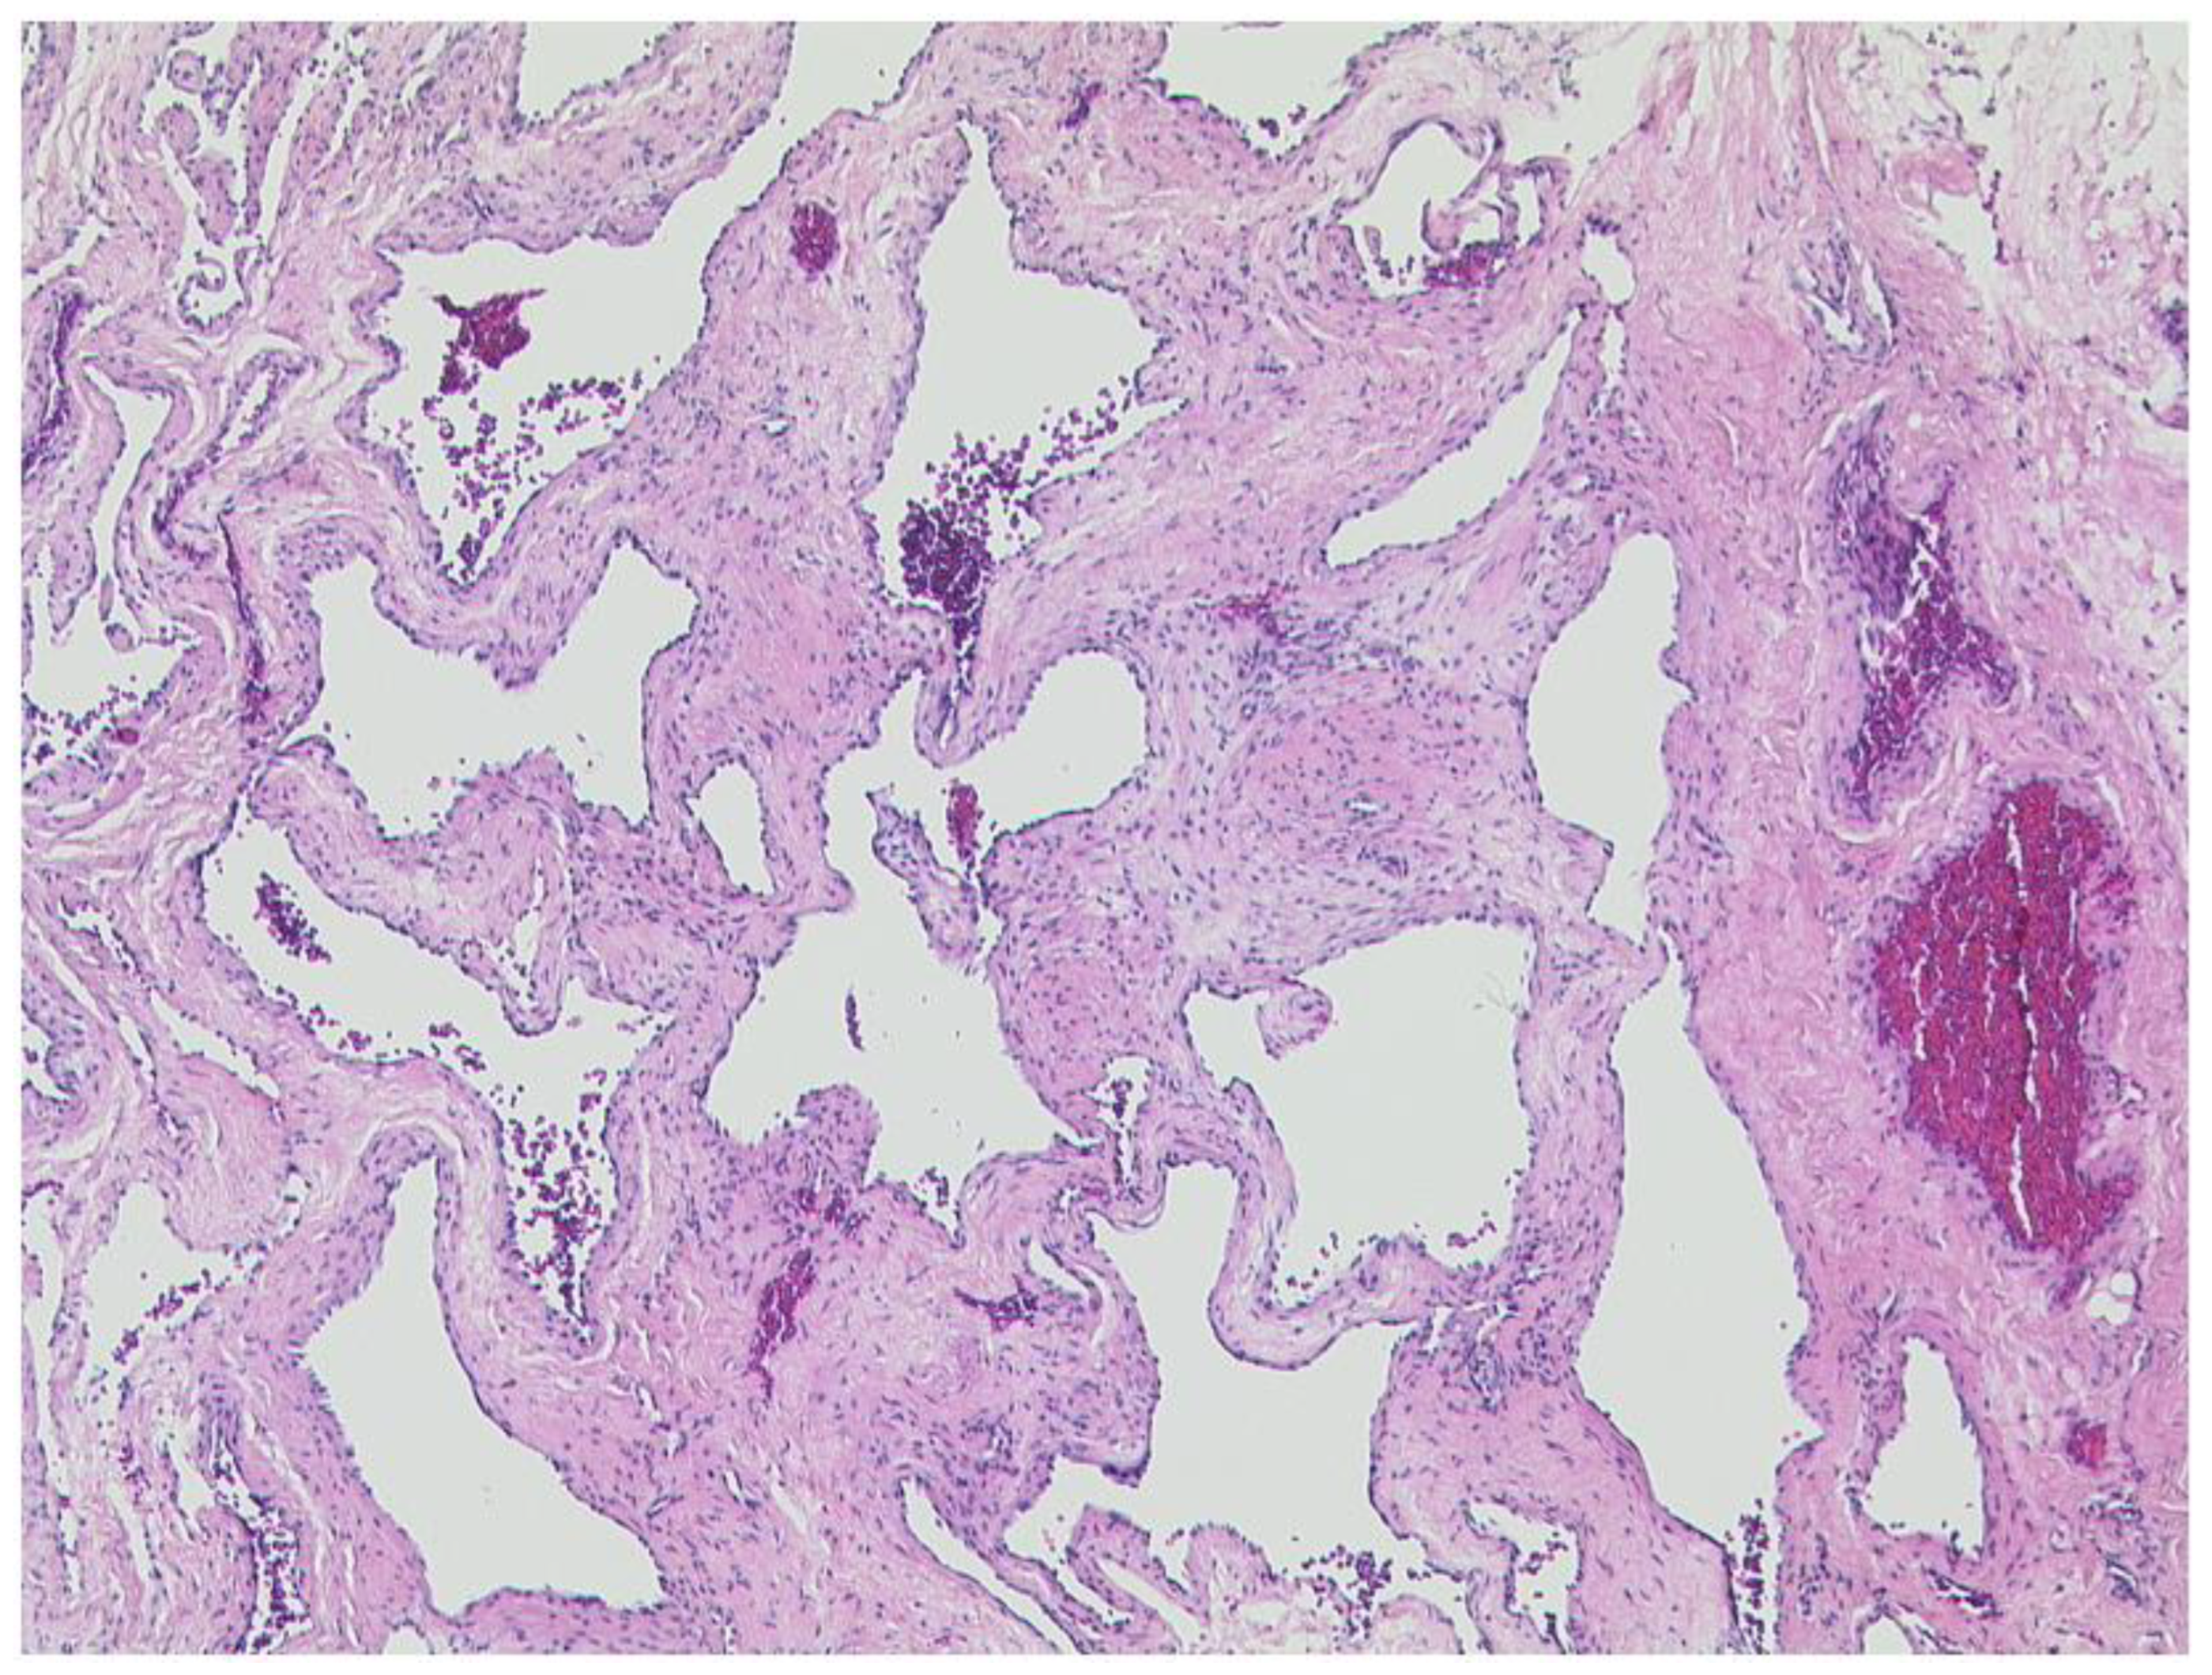

3.2.2. Cavernous Hemangioma

3.3. Extraconal Tumors

3.3.1. Capillary Hemangioma